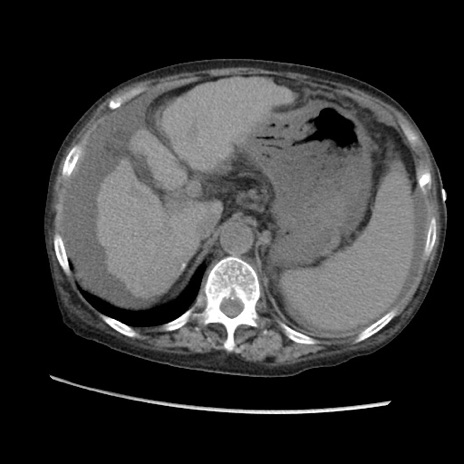

矢状断像